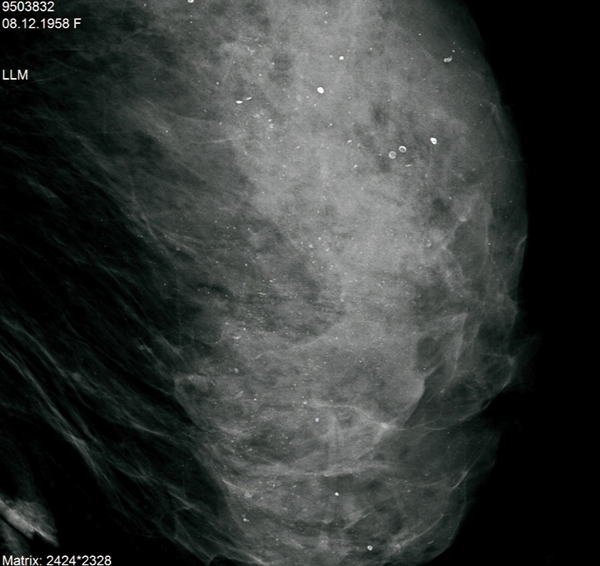

© Sylvie Lemery - La Revue du Praticien Agrandi du profil gauche. Microcalcifications diffuses et bilaterales, non evolutives. BIRADS 2.